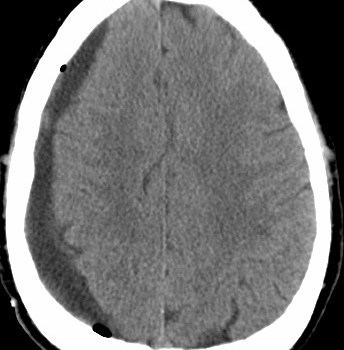

The naked concussion emperor

I’ll be talking about the movie Concussion on WTTW, channel 11 here in Chicagoland. I look forward to talking with Phil Ponce on my second stint on Chicago Tonight (on my first visit, I talked about our work with rats and helping behavior). To anticipate talking about concussions (more so than about the movie), I thought I’d get into the spirit and give […]